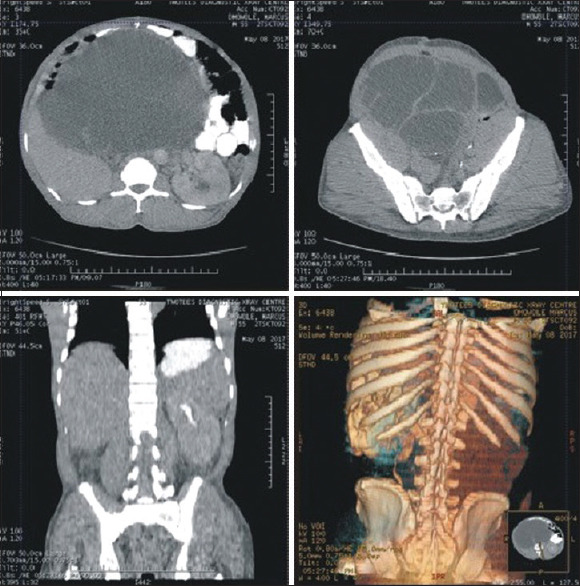

Renal ectopia, even though a benign condition, presents diagnostic challenges when its complications arise. Cold abscess in an abnormally sited kidney may, therefore, create a diagnostic conundrum for the clinician. We present the case of a 55-year-old male who had a suppurating ectopic kidney that mimicked an abdominal visceral mitotic lesion necessitating initial laparotomy, reviewed the literature, and highlighted the need to consider the differential diagnosis, especially in patients who have been referred from peripheral hospitals where generous antibiotic therapy has been instituted. We also recommend undertaking a preoperative split renal scintigraphy where available, especially when nephrectomy is considered.